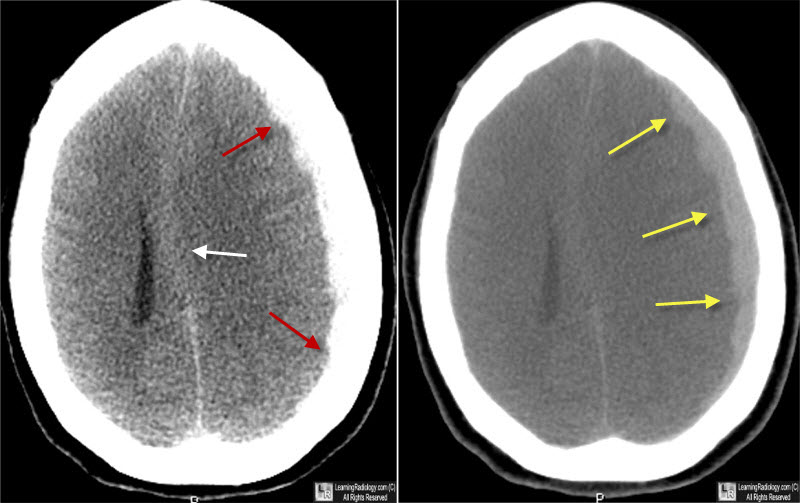

Aspirina en dosis bajas y riesgo de accidente cerebrovascular y hemorragia intracerebral en personas mayores sanas

Este análisis secundario de un ensayo clínico aleatorizado encontró un aumento significativo en el sangrado intracraneal con dosis bajas diarias de aspirina, pero no una reducción significativa del accidente cerebrovascular isquémico. Estos hallazgos pueden tener una relevancia particular para las personas mayores propensas a desarrollar hemorragia intracraneal después de un traumatismo craneal. JAMA Netw Open. 26 de julio de 2023